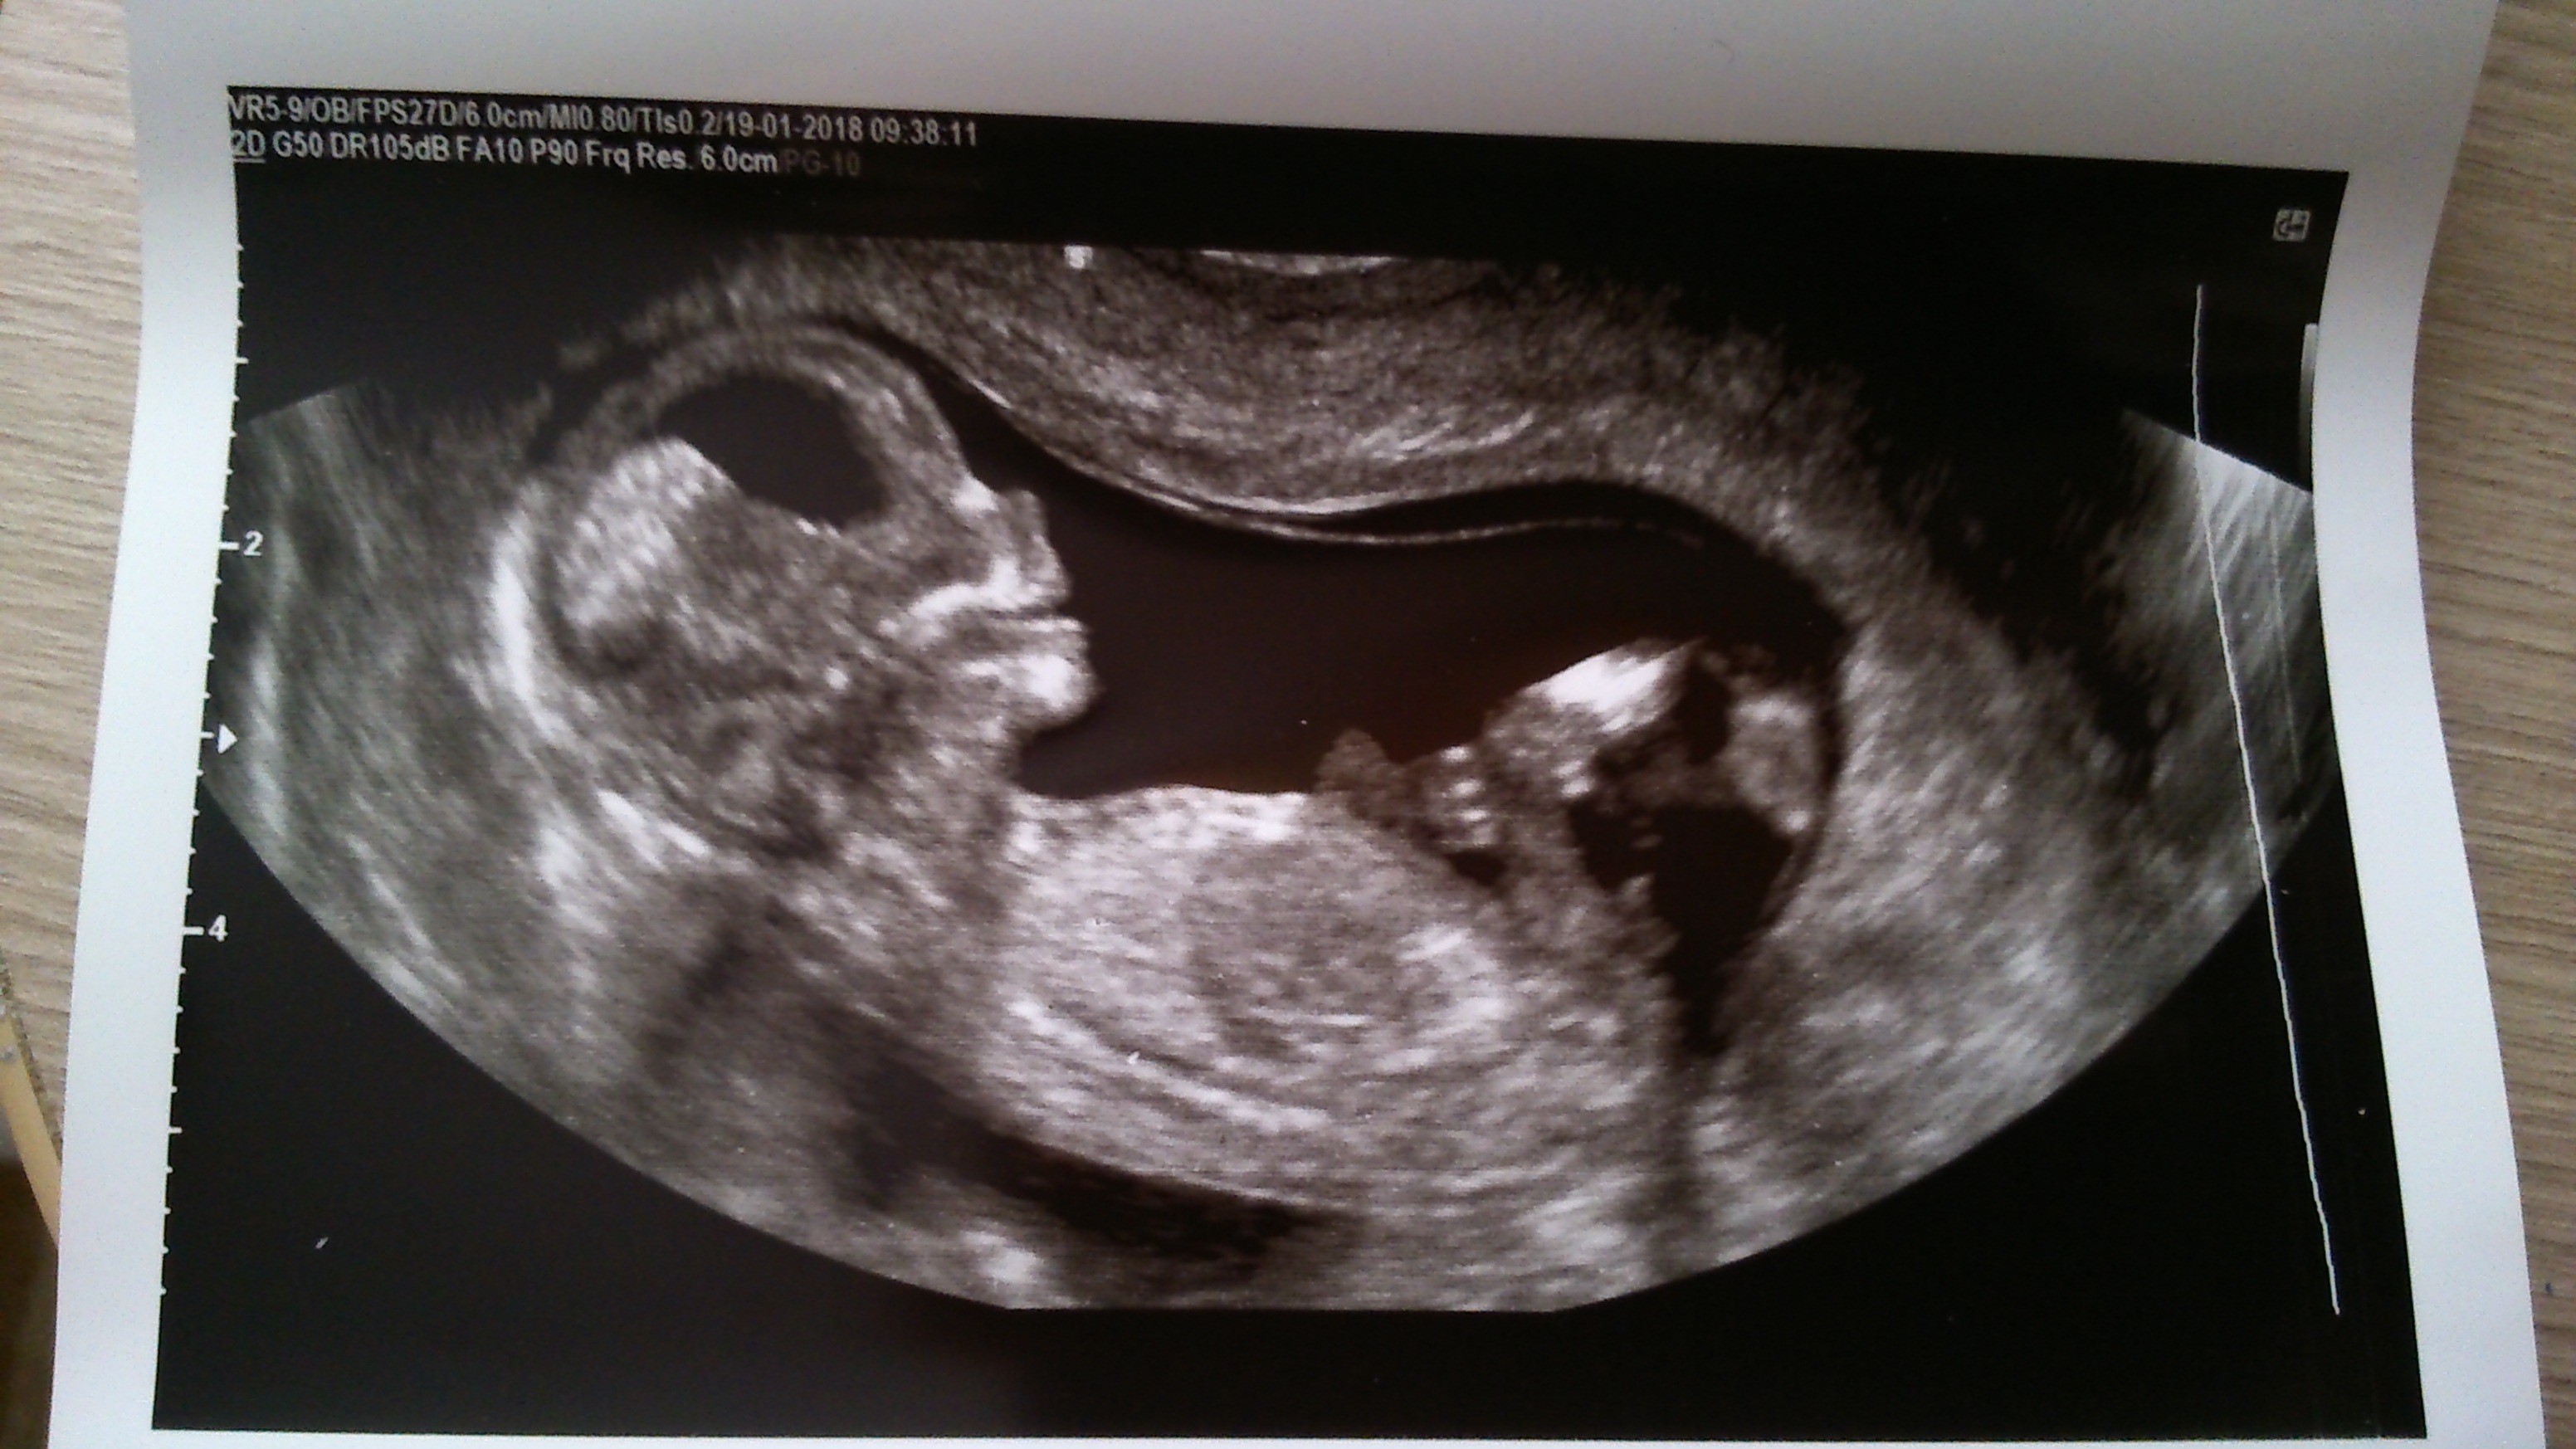

Zobacz załącznik 835942 Zobacz załącznik 835943 Zobacz załącznik 835945 Ja juz po wizycie. Wszystko w porządku jest. Dzidzia strasznie się wierciła. Ale niestety nie chciała się pokazać więc na poznanie płci musze poczekać do 8 marca na usg polowkowe. Maluszek ma już 7 cm. Serduszko 140 ud/min, NT 1,4 mm,

bobas był w super humorze tak się uśmiechał aż buzia otwarta :-)wg usg dzidzia starsza i termin przesunął się na 25 lipiec :-)usg miałam robione przez to i przez to![]()

Cudny Maluszek.. i ta uśmiechnięta buziunia

, Crl 59,17 mm. Z usg 12,6 tc. Skacze, fika, macha łapkami